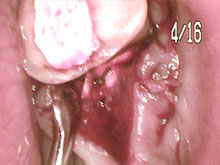

- ( 術前 ) 重度の歯周病になってます。繰り返し歯ぐきが腫れたり、出血を繰り返してました。

- 歯周病のお薬を飲んで頂きました。お薬を飲んで歯石取りをしばらくしました。歯ぐきが引き締まってきました。

- 歯ぐきが引き締まり隙間ができましたので最終的に歯ぐきに合わせて前歯の被せ物を交換しました。